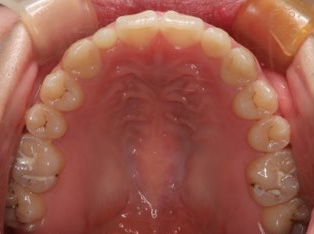

治療前

治療終了前